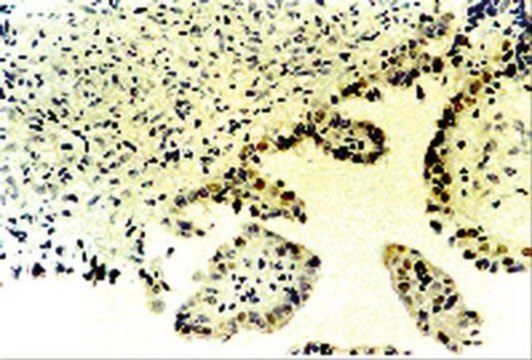

Anti-p73 Antibody, α & β is a Rabbit Polyclonal Antibody for detection of p73 also known as p53-like Transcription Factor & has been validated in IP, WB, IHC(P).

Immunohistochemistry of paraffin sections: Signal amplification may be necessary, in conjunction with standard IHC procedures. Dewax and rehydrate sections through descending graded alcohols to water using standard dewaxing protocols. Subject section to heat antigen retrieval. Wash sections 3 times with TBS, pH 7.4. Block endogenous peroxidase activity by incubating the section in 1% H2O2 in methanol for 30 minutes. Wash with TBS and detect according to preferred detection methods. With high sensitivity detection systems, typical working dilutions for the p73 antibody are 1:5,000 - 1;10,000.

Antibody AB7824 recognizes amino acids 450-636 of p73 protein. This region is common to both p73alpha and p73beta isoforms, hence both isoforms of the p73 protein will be detected.